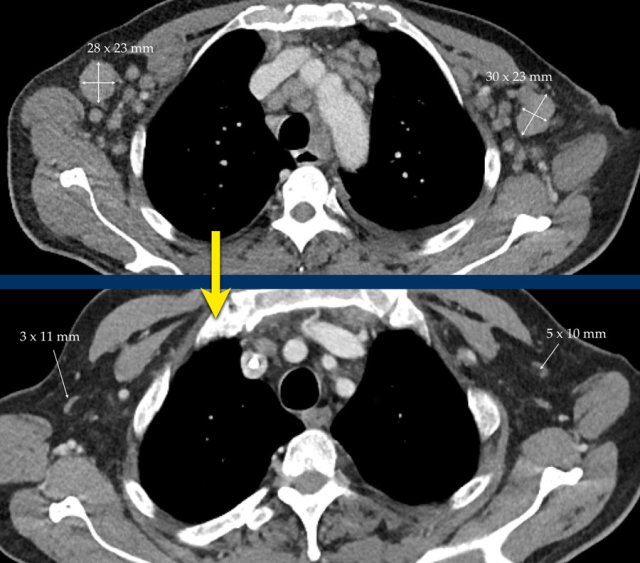

This CT image is of a 61-year-old male with gastric cancer and lymph node metastases.

There is a large lobulated mobile gastric tumor.

We can assume, that on a follow up examination it can not be reproduced in the same way.

Therefore this mobile tumor is not suitable as target lesion, but can be used as non-target lesion.

Continue with next image...

At a lower level there is an enlarged lymph node which is more suitable to be used a target lesion (arrow).